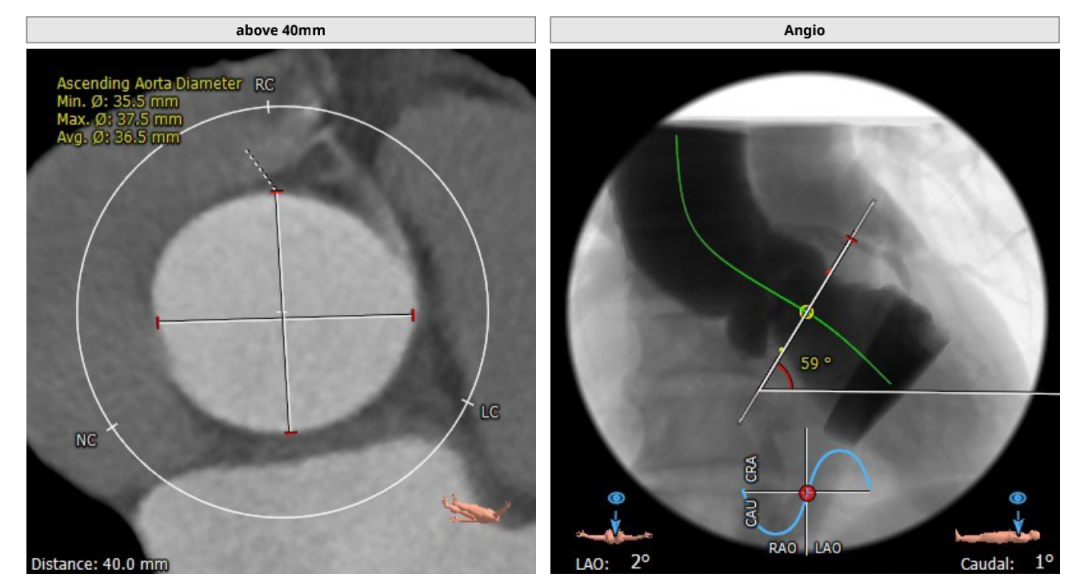

CT评估

瓣环直径:24.5mm,左室流出道直径:25.4mm

主动脉窦:25.9*36.9mm,STJ:30.4mm

升主动脉直径:36.5,心脏夹角:59度

左冠高度:20.1mm,右冠高度:19.5mm